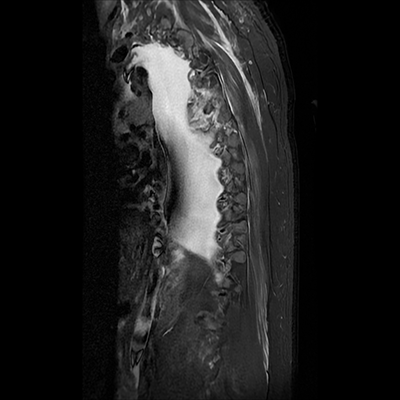

MRI T-spine (sagittal STIR)

For simplicity's sake, only his sagittal STIR images were included here. When reviewing spine imaging, it's important to also review the axial images.

In his thoracic spine, however, we can see some obvious abnormalities. There's severe canal narrowing at T4-T5 with intrinsic cord signal change, T4 fracture, and T5 fracture (three-column injury!).